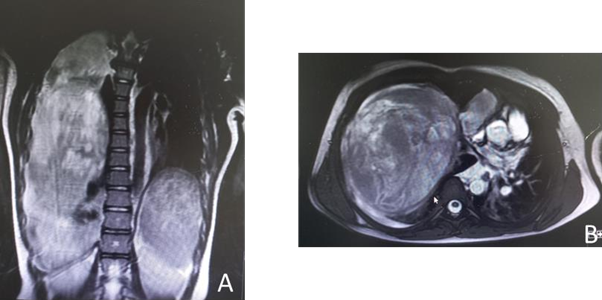

The thoracic scan showed a large tumor measuring 17 x 13 x 11 cm that caused an almost complete collapse of the right main pulmonary artery and deviation of the mediastinum to the contralateral side (Figure 2). The study was completed with a chest MRI, limited by the patient's instability. Comparing it with the previous scan, a greater content of active bleeding was observed at the level of the right lower lobe (Figure 3A, B).

Figure 3

A. MRI findings show that the mass apparently has intrapulmonary characteristics.

B. The anterior and inferior chest wall contacts the mass without being able to rule out wall involvement.